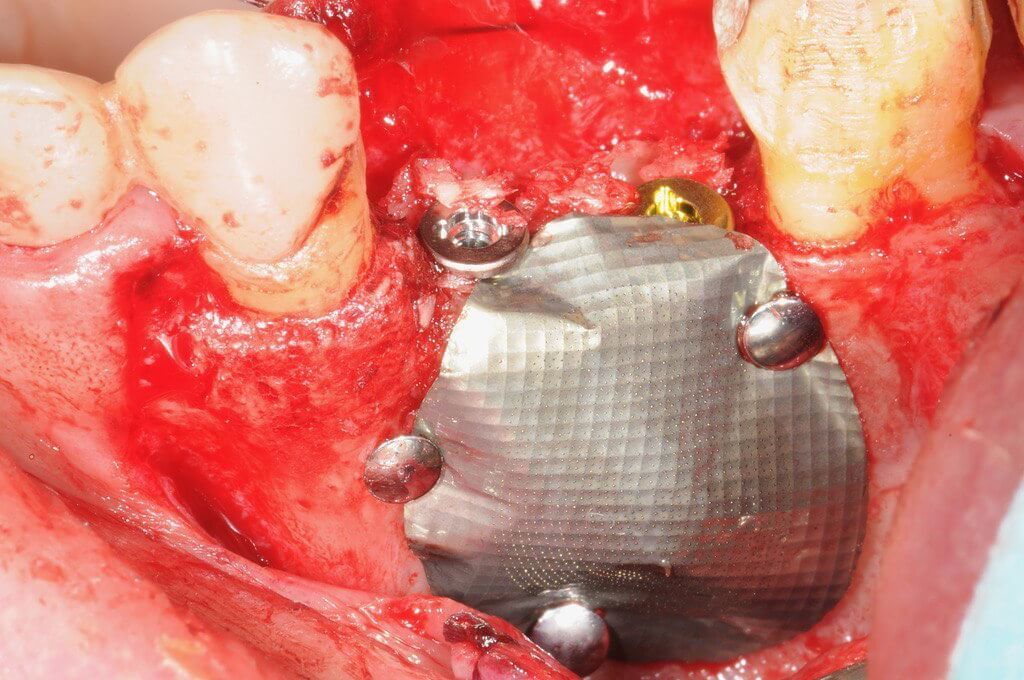

Имплантаияпри одновременном восстановлениигоризонтальных дефектов челюсти - не«сосидж»

Имплантация. Принципиальное значение костной и мягкой тканей